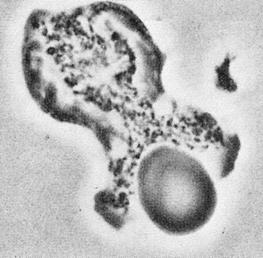

Рис.4 Стадии фагоцитоза.

1. Хемотаксис 2. Адгезия

3. Поглощение чужеродного агента (эндоцитоз). 4. Внутриклеточное переваривание объекта.